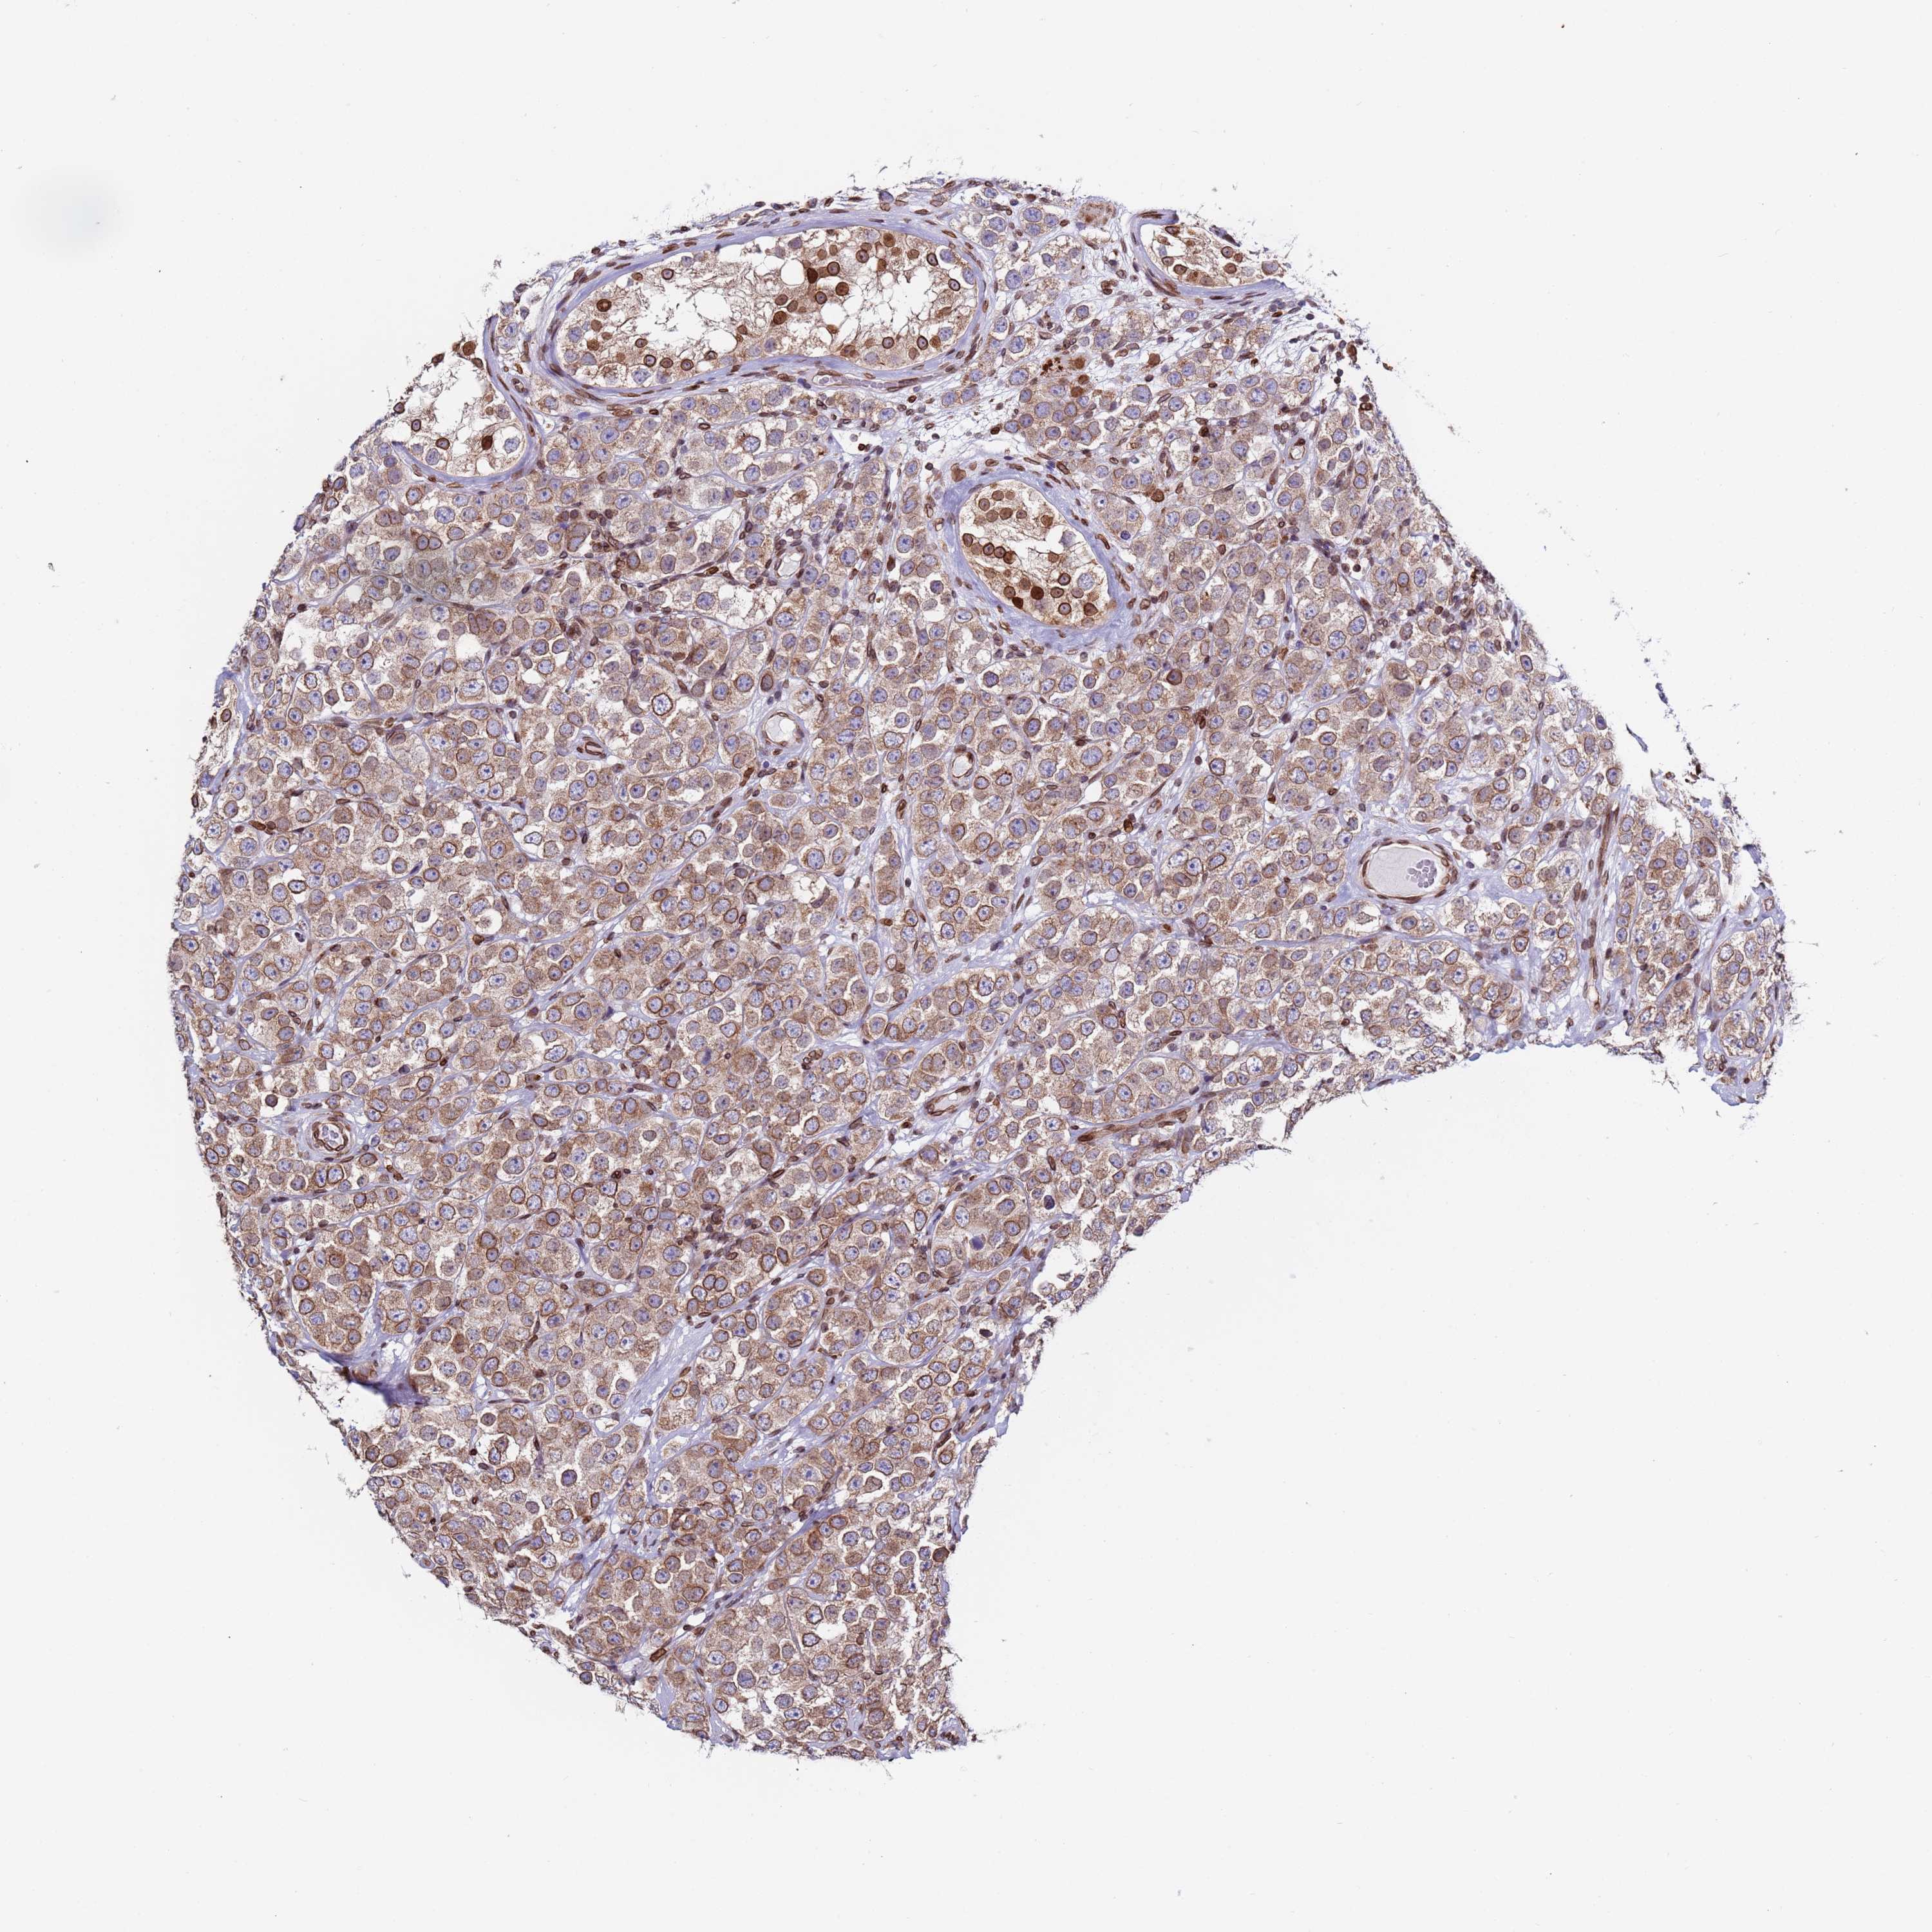

TESTIS CANCER - Protein expressioni

A mouse-over function shows sample information and annotation data. Click on an image to view it in a full screen mode. Samples can be filtered based on level of antibody staining by selecting one or several of the following categories: high, medium, low and not detected. The assay and annotation is described here.

Note that samples used for immunohistochemistry by the Human Protein Atlas do not correspond to samples in the TCGA dataset.

Antibody stainingi

Antibody staining in the annotated cell types in the current human tissue is reported as not detected, low, medium, or high, based on conventional immunohistochemistry profiling in selected tissues. This score is based on the combination of the staining intensity and fraction of stained cells.

Each image is clickable and will lead to virtual microscopy that enables deeper exploration of all samples and also displays staining intensity scores, fraction scores and subcellular localization as well as patient and tissue information for each sample.

Antibody HPA050546

Seminoma, NOS

Carcinoma, Embryonal, NOS